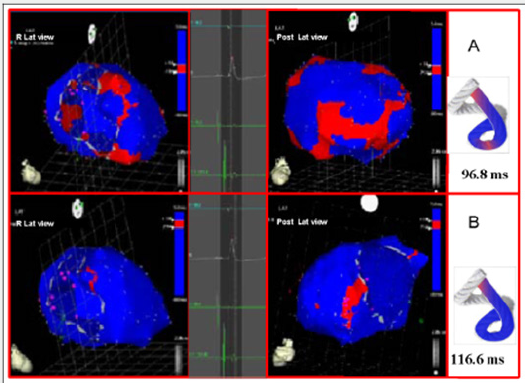

The EAM took an average of 20 minutes per patient. There were no complications Figures 3-5 illustrate endo and epicardial propagation of electrical activation. In all figures, the left panel shows the right lateral projection and the right panel the simultaneous left anterior oblique projection. The activated areas at each moment are seen in red. The lateral part represents the activation of the bands in Torrent Guasp’s rope model [1], where the depolarized zones are shown in red and previously activated zones in refractory period in blue. Below the rope can be seen the average propagation time of electrical muscle band measured in ms on the site analyzed (Table 1). This analysis was performed correlating the path of the stimulus with Torrent Guasp’s rope model of the cardiac band.

The Figures 4B, 5A & 5B show the progress and end of this process. In Figure 5A it can be seen that endocardial activation finishes much earlier than the end of the QRS period; the rest of the QRS period corresponds to the late activation of the distal portion of the ascending band, explaining its persistent contraction during isovolumic diastole, which is the basis of the ventricular suction mechanism (Figure 5B). Figure 6 (upper panel) summarizes the stimulation of this rope model found in this investigation.

Figure 5: A: Late activation of the ascending band. At this moment, corresponding to approximately 60% of QRS duration, endocardial activation (descending band) has already been completed. The distal portion of the ascending band (epicardial) depolarizes lately. This phenomenon correlates with its persistent contraction at the initial phase of diastole. B: Final activation. In the right panel, the projection was modified from left anterior oblique to left postero-lateral, showing the very late activation of the distal portion of the ascending band.